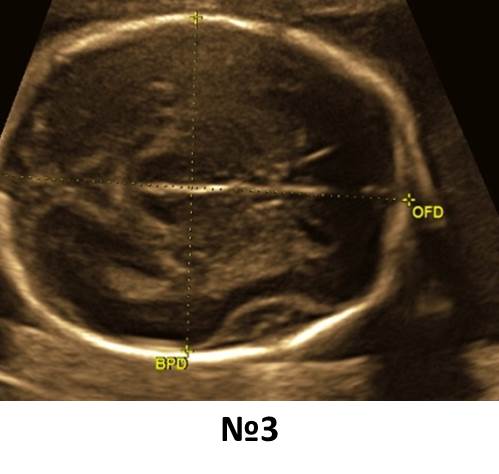

Вопрос 3

Какое из измерений корректно для оценки заднего рога бокового желудочка? Что еще нужно обязательно заархивировать при оценке задних рогов?